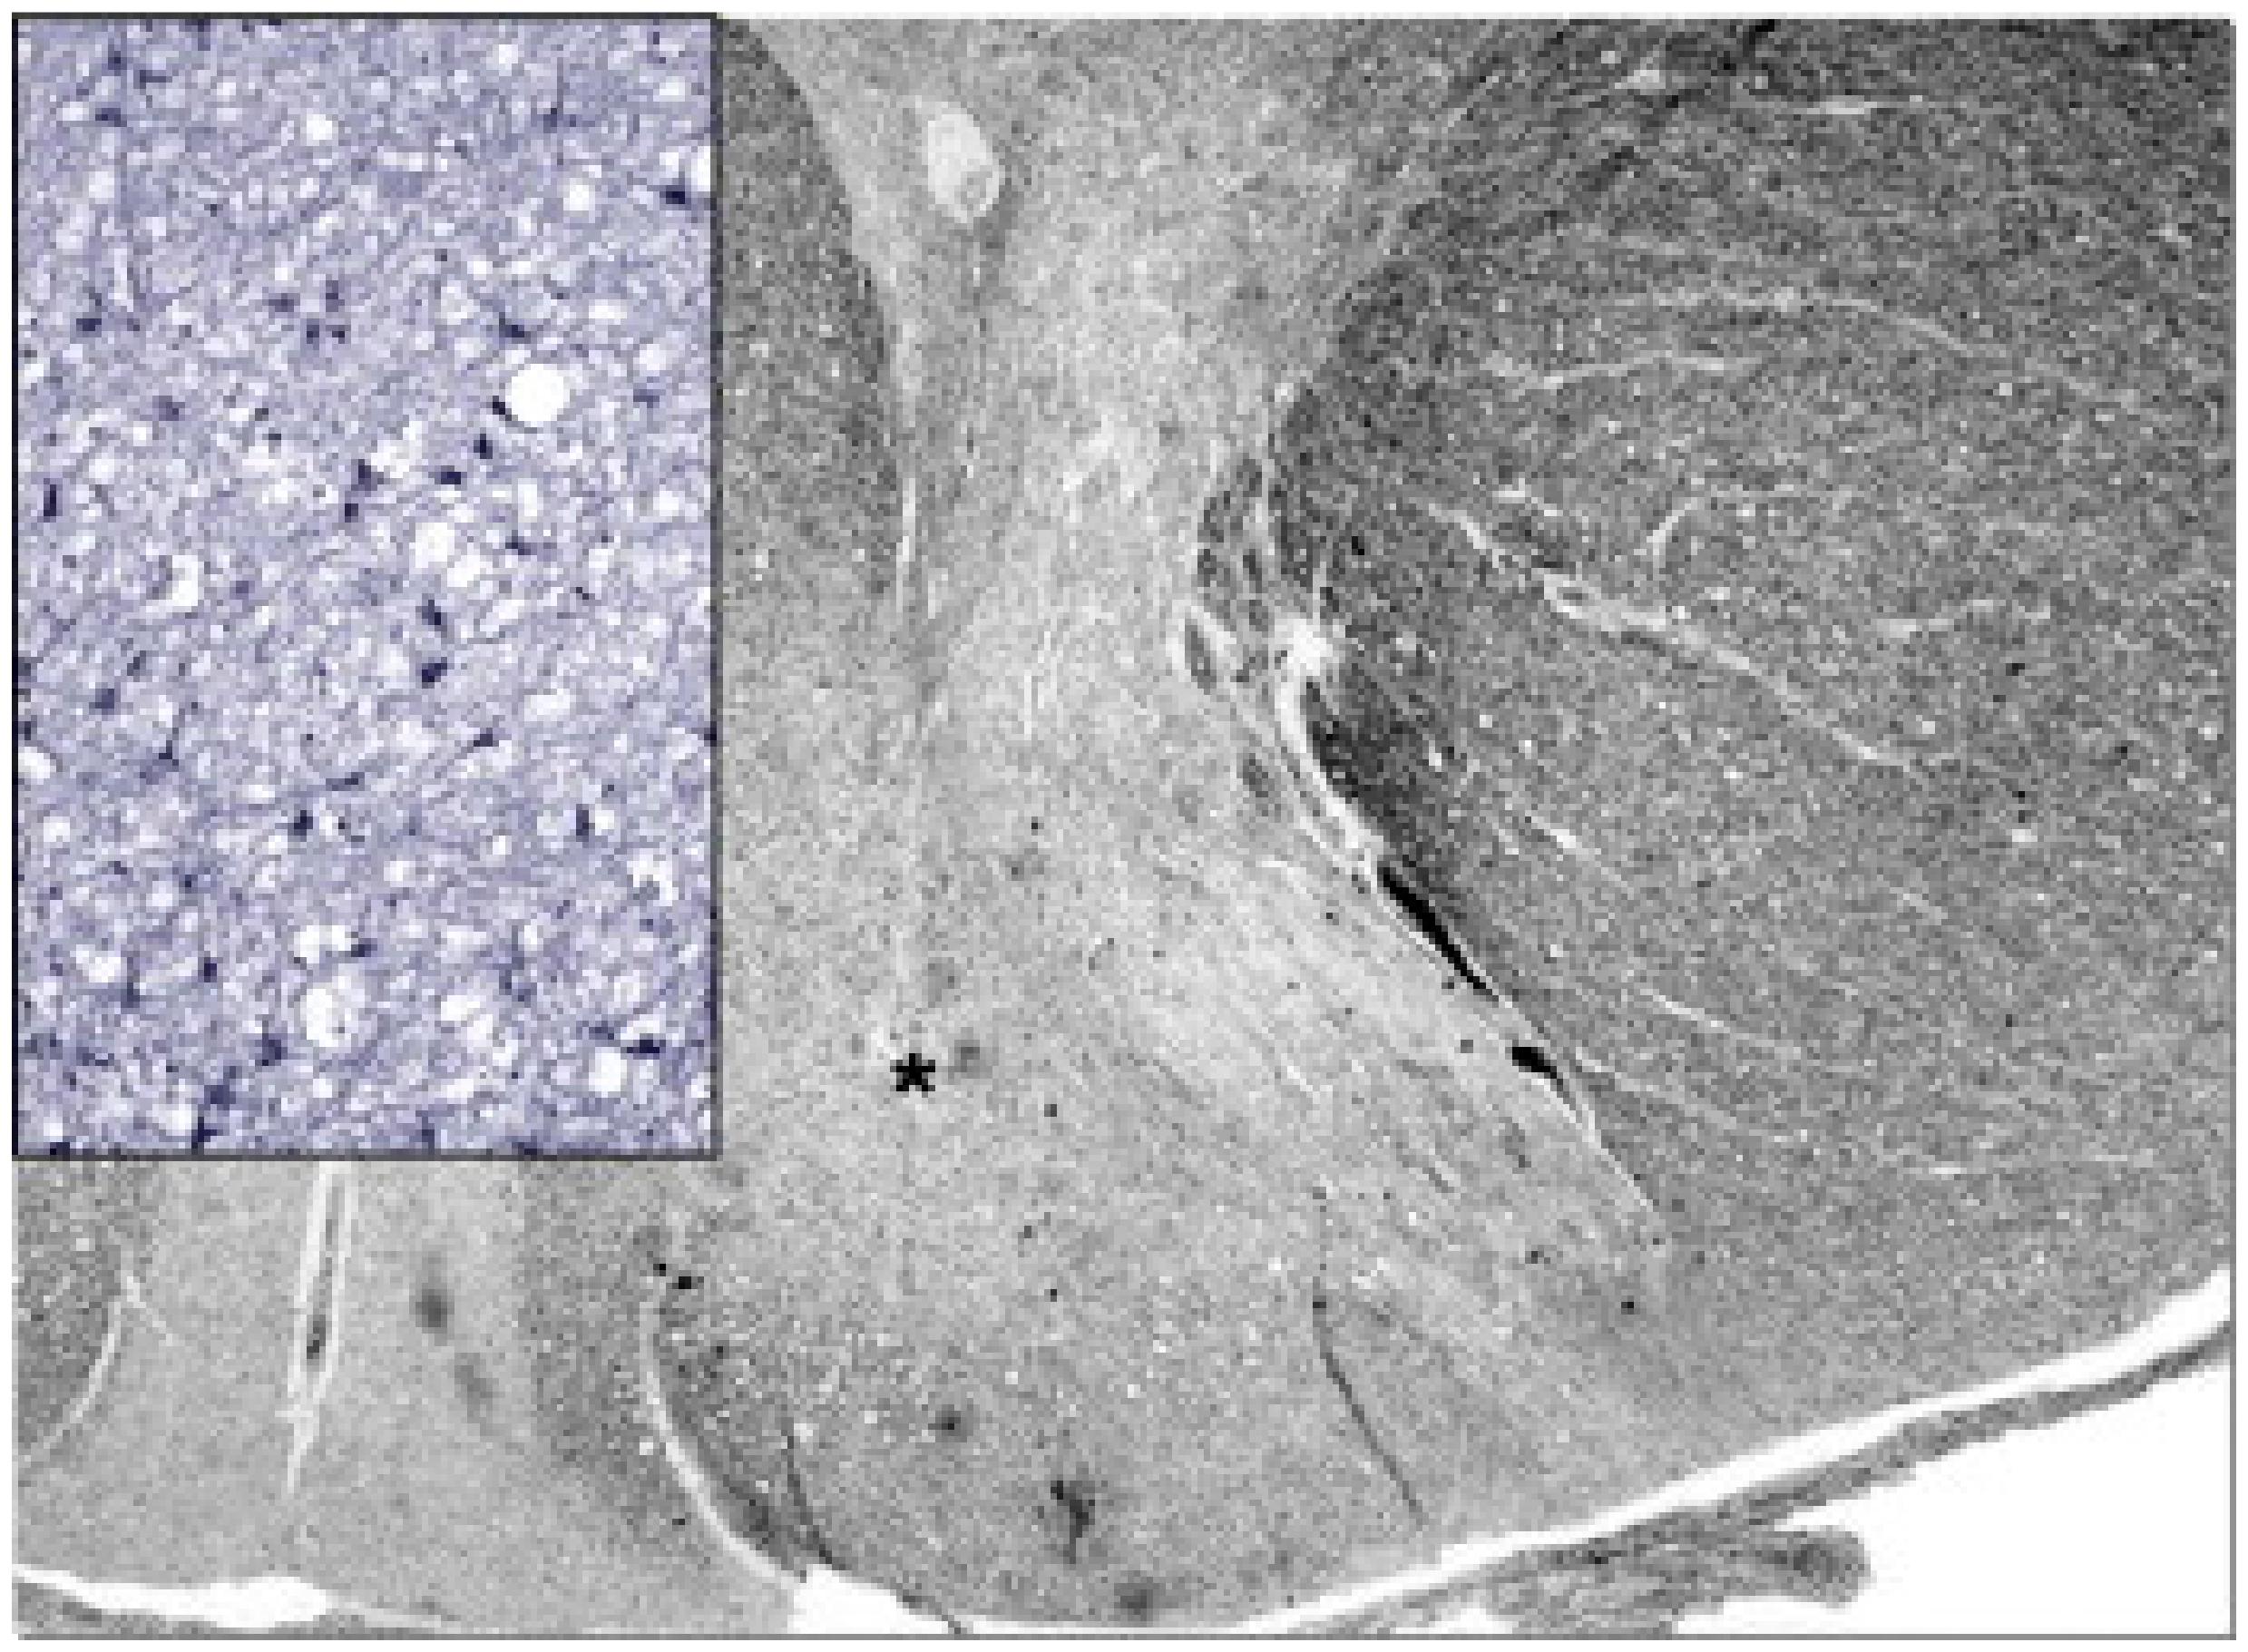

- Simonati, A.; Filosto, M.; Savio, C.; Tomelleri, G.; Tonin, P.; Dalla Bernardina, B.; Rizzuto, N. Features of Cell Death in Brain and Liver, the Target Tissues of Progressive Neuronal Degeneration of Childhood with Liver Disease (Alpers-Huttenlocher Disease). Acta Neuropathol. 2003, 106, 57–65. [Google Scholar] [CrossRef] [PubMed]

- Filosto, M.; Tomelleri, G.; Tonin, P.; Scarpelli, M.; Vattemi, G.; Rizzuto, N.; Padovani, A.; Simonati, A. Neuropathology of Mitochondrial Diseases. Biosci. Rep. 2007, 27, 23–30. [Google Scholar] [CrossRef]